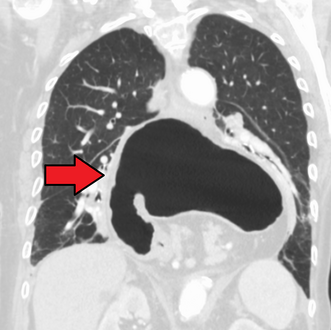

يتم تشخيص فتق الحجاب الحاجز عادةً من خلال سلسلة تصوير الجهاز الهضمي العلوي، التنظير الداخلي، قياس الضغط عالي الدقة، مراقبة درجة حموضة المريء، والتصوير المقطعي المحوسب. يسمح ابتلاع الباريوم كما في سلسلة تصوير الجهاز الهضمي العلوي لرؤية حجم المريء وموقعه وتضيقه. كما يمكنه تقييم حركات المريء. يمكن للتنظير الداخلي تحليل السطح الداخلي للمريء بحثاً عن التآكلات والقرح والأورام.

وفي الوقت نفسه، يمكن لقياس الضغط تحديد سلامة حركات المريء ووجود ارتخاء المريء. وتسمح اختبارات الأس الهيدروجيني بالتحليل الكمي لنوبات الارتجاع الحمضي. كما أن التصوير المقطعي المحوسب مفيد في تشخيص مضاعفات الفتق الحجابي مثل الالتواء المعدي، واسترواح الصفاق، واسترواح المنصف.[8]

تنظير الجهاز الهضمي العلوي يصور الفتق الحجابي.